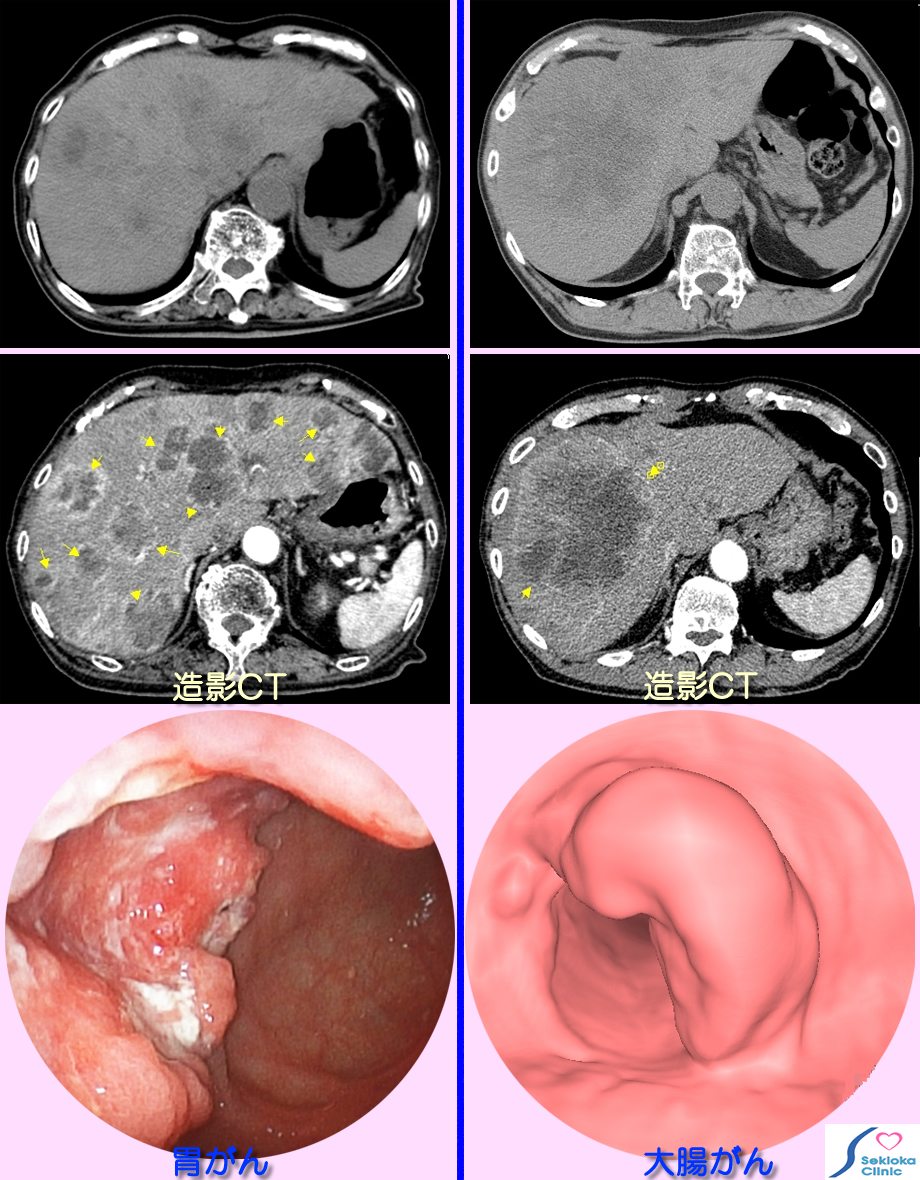

| 診断 | がん転移早期には血液検査では異常を認めないこともあります。ある程度大きくなるとアルカリホスファターゼ、AST、ALT、ビリルビンなど上昇。画像診断の方が血液検査より早期に転移が見つかることは多い。超音波エコー検査、CTなどの画像診断が行われます。下段左列の画像は、食欲不振、体重減少、軽い上腹部痛でCT検査を行ったところ肝内にX腺低吸収の領域(黒い)を多数認め、がんの転移を疑い、精査のため造影剤を用いてCT検査を行った画像が中段です。多数の内部が低吸収(黒く)で周囲は血管が豊富な(白い辺縁)結節を認め、転移性がんを疑い、内視鏡検査で進行した胃癌を認めた例です。右側は胸部CT検査で偶然肝臓内に低吸収(黒い)領域を認め、造影剤を用いたCT検査(中段の画像)から肝臓への転移がんを疑い、大腸CT検査で最下段の画像のごとく、大腸癌を認めた例です。 |